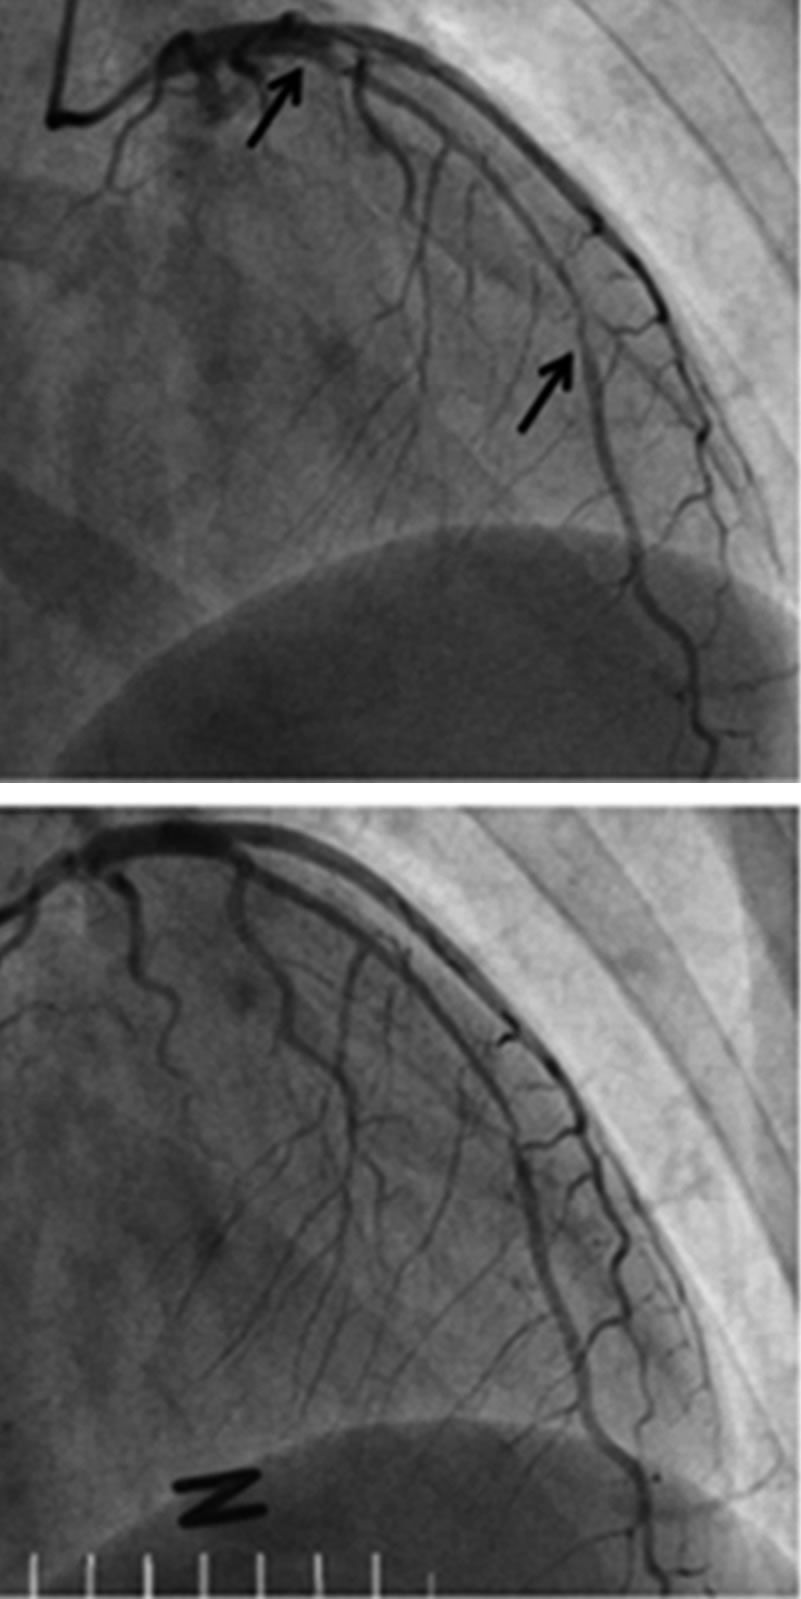

Learn the Signs of Spontaneous Coronary Artery Dissection

This unusual condition may be greatly underdiagnosed. But knowing the warning signs are important, becasue it presents as a heart attack.